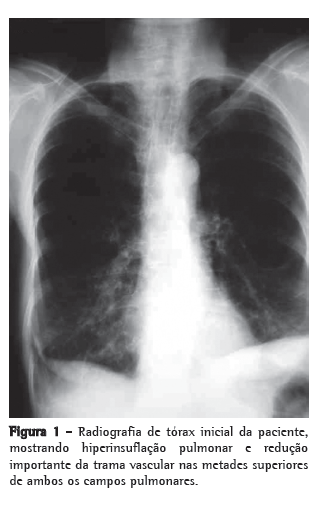

Encontrava-se em uso de levotiroxina, calcitriol e prednisona 15 mg/dia, mas já havia feito uso de metotrexato previamente. Ao exame físico, apresentava-se emagrecida (30 kg de peso e índice de massa corpórea de 14 kg/m2), sem linfonodomegalia cervical ou supraclavicular e sem baqueteamento digital. A ausculta pulmonar revelou apenas murmúrio vesicular reduzido difusamente. A radiografia de tórax no início do quadro, há 4 anos, mostrava hiperinsuflação pulmonar e redução importante da trama vascular nas metades superiores de ambos os campos pulmonares (Figura 1), e a TCAR realizada revelara enfisema parasseptal, cavidades e destruição do parênquima com predomínio nos lobos superiores (Figura 2). A gasometria arterial e o teste tuberculínico não revelaram anormalidades. A espirometria mostrou distúrbio ventilatório obstrutivo incipiente, sendo iniciado tratamento com formoterol. No último ano, com a piora dos sintomas, a paciente foi submetida à nova TCAR, que mostrou piora do padrão radiológico (Figura 3). A baciloscopia direta do escarro foi negativa para BAAR. O método Gomori-Grocott com prata metenamina evidenciou formas leveduriformes intracelulares, e as culturas das amostras de escarro e do lavado broncoalveolar em ágar dextrose Sabouraud revelaram a presença de Histoplasma capsulatum. Foi iniciado tratamento com itraconazol, 200 mg/dia.(8) A paciente encontra-se em acompanhamento ambulatorial com melhora sintomática e aumento de peso.